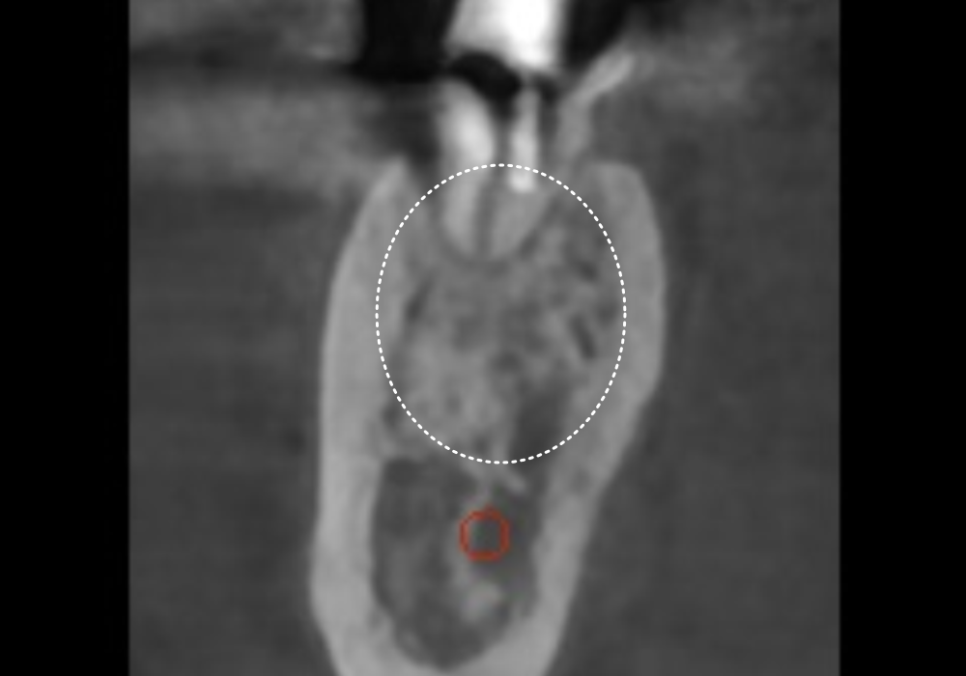

3D CT를 볼까요?

빨갛게 표시한 부분은

아래턱의 감각을 담당하는 주요 신경인

하치조 신경이고,

노란색 부위가 염증으로 인해

뼈가 녹아버린 공간이에요.

임플란트를 심을 때 가장 중요한 것은

이 신경을 피해 안정적으로 식립하는 것인데요.

이 상태에서 바로 심게 되면

뼈가 녹아 텅 빈 공간에 임플란트 뿌리가

제대로 고정될 수 없겠죠~

또한 임플란트가 지지력을 얻으려면

최소 7~8mm의 뼈 길이가 확보되어야 하는데,,

사진을 보면 뼈가 녹은 지점부터

신경까지의 거리가 거의 닿을 듯 가깝습니다.

이런 경우 무리하게 바로 심다가는

자칫 신경을 건드릴 위험이 커요.

그래서 이런 케이스의 경우,

뼈가 먼저 튼튼하게 회복하기를 기다려준 뒤,

뼈가 안정적으로 생성이 되면

임플란트를 식립해야 합니다.